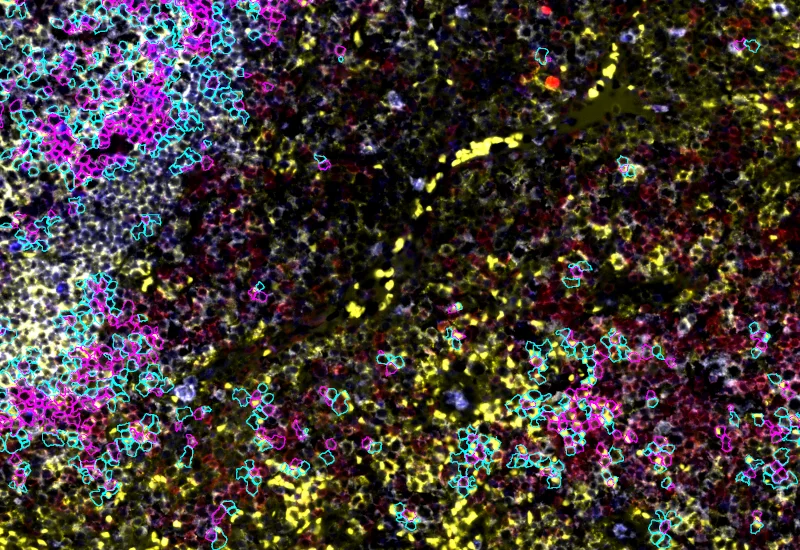

Original Image

Phenotype 1 and Phenotype 2 detection